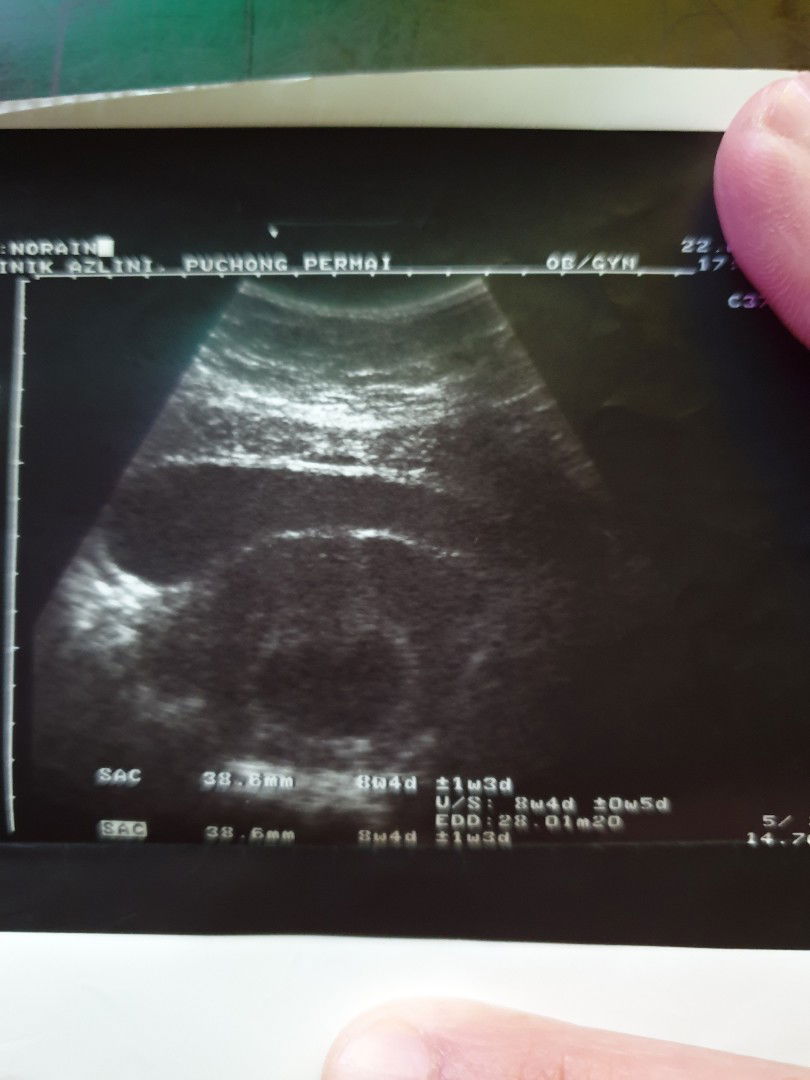

Alhamdulillah, 7tahun menanti. Akhirnya doc sahkan mengandung 12w. Bersyukur sgt2..

7 tahun menanti, akhirnya doc sahkan mengandung 12w, Alhamdulillah sgt2 bersyukur.